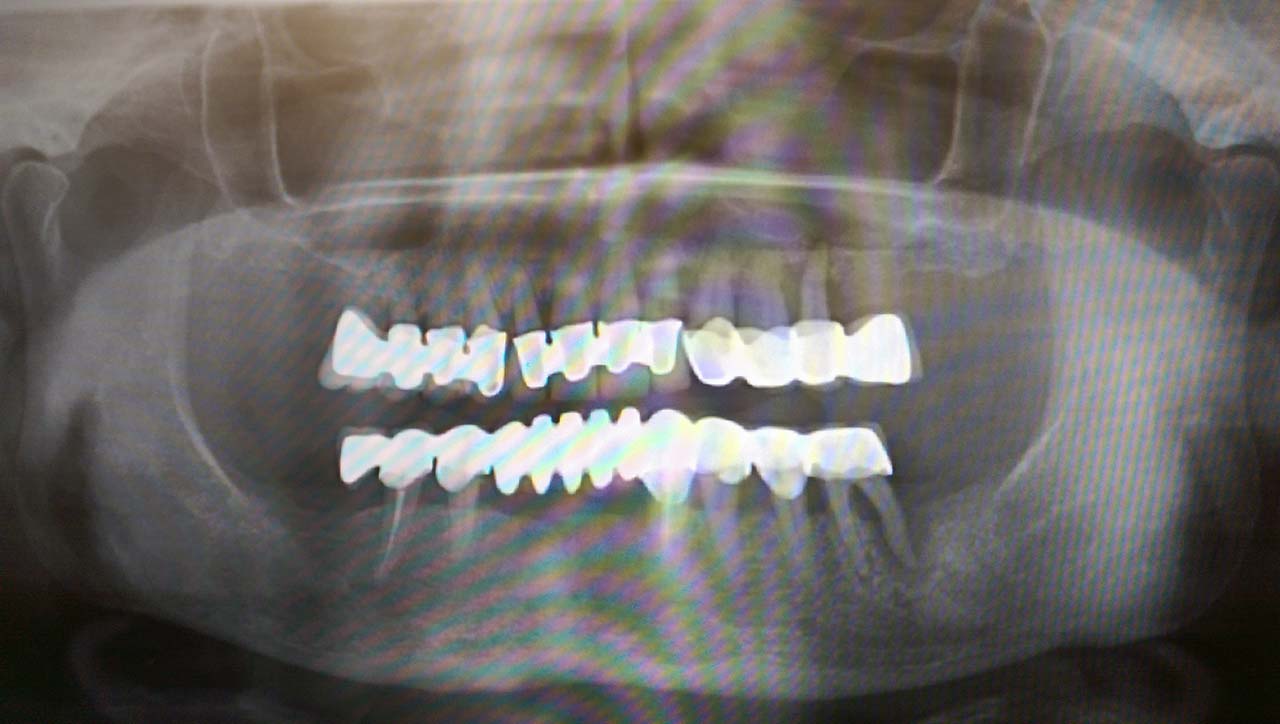

2 nap alatt varázsoltuk ezt a szép esztétikus alsó, felső körhídat implantátumokkal megtámasztva a korábban elhanyagolt szájba. Az 1. nap 26 fogat távolítottunk el, mert annyira rossz állapotban voltak, és rögtön azonnal terhelhető IHDE svájci implantátumokat raktunk be, fentre 8, lentre 6 darabot. A sebeket összevarrtuk és intraorális szkennerrel digitális lenyomatot vettünk. 2 nap múlva pedig beragasztottuk a kész PMMA műanyag körhidakat. Dr. Kelemen Péter és a Symbion Fogtechnika munkája.

Teljes fogatlanság helyreállítása 2 nap alatt azonnal terhelhető svájci IHDE implantátumokkal és PMMA műanyag hidakkal. Intraorális szkennerrel vettünk lenyomatot az implantáció után, és erre a digitális mintára készítette el a fogtechnika a hidak digitális tervezését, majd faragta ki műanyagból. Ezt a gyors munkát az azonnal terhelhető implantátumok és a digitális lenyomat, tervezés segítségével tudtuk megcsinálni mindössze 2 nap alatt. Dr. Kelemen Péter és a Symbion Fogtechnika munkája.